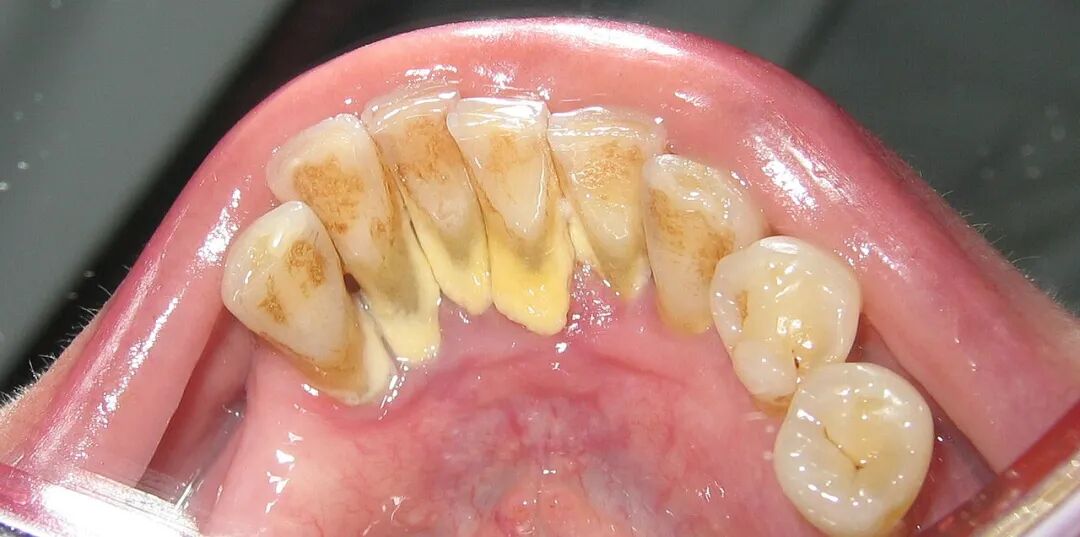

牙齿上的牙结石(牙根处黄色部分) 图源:wikipedia

这也解释了为什么牙结石最容易出现在下门牙内侧、上后牙的外侧,这些位置都是唾液腺开口处,矿物质源源不断供应,堪称牙结石的“高产区”。